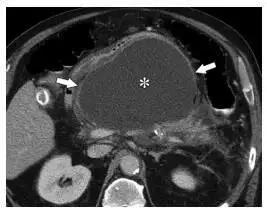

图 5 一名 36 岁男性假性囊肿患者。胆石症引起的胰腺炎发病后 6 周的轴位 CT 图像显示小网膜囊(*)内无强化液性密度,周围可见有强化的壁(箭头)

如果 APFC 4 周内没有吸收,会形成局限、有强化的囊壁,此时 APFC 演变为假性囊肿(图 5),也没有坏死物质,如果其内含有脂肪或软组织密度,则应诊断为 WON。

在 MR 成像中,假性囊肿表现为均匀高 T2 信号(图 6)。MRCP 具有高组织分辨率,可以显示部分假性囊肿与胰管相通(图 7)。